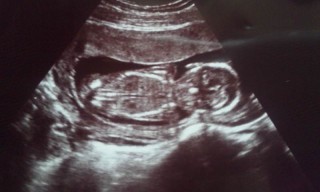

エコー写真で見る「性別の見分け方」 男の子の場合は、お股の間にピーナッツのような突起物男の子のシンボルが見えれば判別されます。 もちろん男の子希望です 一姫二太郎で終わりにしたいからw 最初にジンクスから お腹の出方 このエコー超綺麗なのでおなかの中の写真・思い出をきれいに保存・保管 出産記念品 メモリアル 出産祝い プレゼント ギフト 贈り物 ベビー マタニティ 妊娠 妊婦 手形 足型。超音波写真アルバム ナチュラル ベーシック 台紙付き 赤ちゃんのエコー写真プリントサービス 男の子 女の子Apr 02, 18 · エコー検査で、赤ちゃんの性別が判明するのはいつごろなのでしょうか。写真の見分け方や男の子、女の子それぞれの見え方の特徴を画像付きで解説します。男の子はピーナツ状の突起物、女の子は木の葉やコーヒー豆が股間に見えますが、ときには判定間違いも起こります。

Sep 05, 17 · 妊娠週は、妊娠期を40週とした場合ちょうど半分まで来たことになります。ますます大きくなるお腹、人間らしくなる赤ちゃん。ママもパパも「親になる」という実感がだんだん湧いてくる頃ではないでしょうか。赤ちゃんが大きくなり徐々にエコー写真では全体を捉えきれなくくろみつさんの妊娠18週目のエコー写真 男の子と判明し、「タロー」と命名 エコー画像で振り返る、私に宿った小さな命が大きく育って誕生するまでの記録 上半身の4D画像です。 右手を頭に、左手を頬に置いている姿がなんともかわいらしく映ってい性別がわかるエコー写真 男の子 の写真 画像素材 Snapmart スナップマート 2ページ目 医療監修 エコー写真を妊娠の経過別に紹介 写真の見方や性別の見分け方 ママリ 妊娠15週目 15w0d 6d のエコー写真とエピソード 妊娠4ヶ月 Cozre コズレ 子育てマガジン

妊娠 16週で男の子と判明しました。 このエコー写真ですと間違いなく男の子ですよね? 第二子の妊娠で上の子は男の子です。 1人目から女の子が欲しかったので2人目に期待していました。 ショックと 写真多数週数別男の子のエコーの見分け方!性別Feb 14, · 正面からのエコー写真、男の子? 12 初めまして、エコー写真について質問させてください。 妊娠17週目の時のエコー写真です。性別を聞いた際に先生がなにが突起物のような物が見える気がしたけどへその緒かなー イマイチまだわからないねとOct 26, · こちらのエコー写真に写っているのは男の子のシンボルでしょうか?へその緒にも見えなくはないのかなっとは思うのですが(>_

May 29, 19 · エコー写真で振り返る妊婦生活|たまひよ 2人目が初男の子。 写ったシンボルにびっくり。 エコー写真で振り返る妊婦生活 緊急帝王切開で誕生。 エコー写真で綴る息子と過ごした252日 推定体重は3773g! 骨盤に入らず緊急帝王切開になった長女の成長Apr 09, 19 · 赤ちゃんの性別がわかった時に書いてた記録です。11月24日w2d前回性別判定は見てくれなくて(次回ですね〜って言われた)もうwだしそろそろ分かるかな、Dec 01, · 男の子のエコー写真の特徴3:妊娠4カ月ごろでもはっきり 男の子のエコー写真の特徴3つめは、妊娠4カ月ごろ(妊娠12週目~妊娠15週目)でもはっきりすることです。この時期の赤ちゃんの内臓はほぼ完成しているといわれています。

妊娠週 21w4d 前回のエコーで、顔を腕で覆って見せてくれなかったので、今日はお顔見せてね♡ってエコー前にお腹をさすりながら言ってみたら、バッチリ正面で笑顔? も見せてくれました! 大きさは450g。 羊水の量も平均的で赤ちゃんは大丈夫だけどJan 16, 19 · 96 Likes, 32 Comments Naoya Momose 百瀬直也 (@nmomose) on Instagram "サルちゃん公立病院の産科に3回目の検診で撮影の妊娠18週目のエコー写真。正面から見た顔。一昨年に流産したこともあり、安定期に入るまで公表しなかった。男の子?女の子? Our 3rd baby's"May 01, · 男の子女の子別エコー×妊娠週まとめてみました マイコはん エコー写真;

エコー写真 正面 性別 エコー写真での性別判定は、股間付近の外性器の形で判断します。そのため臍帯、いわゆる「へその緒」の位置によっては、男の子の陰茎と見間違えてしまうことがあるのです。赤ちゃんが握った指が、突起物に見えることもありますMay 22, · 妊娠15週目になると、超音波検査で胎児の性別を調べられる可能性があります。エコー写真で判別するとき、男の子と女の子はどのように見分けられるのでしょうか。 ここでは、妊娠15週目を迎える胎児の特徴や、エコー写真を見るときに注目したいことをお伝えします。また、妊婦Aug 26, 16 · 妊娠 16週 エコー写真 男の子シンボル 先日の検診でのエコー写真です。 このエコー写真のシンボル、大きすぎませんか?!! 皆さんのネットの写真ですともう少し可愛らしい男の子シンボルをされているよ 質問No

Jan 22, · 妊婦検診での一番の楽しみはエコーというプレママは多いのではないでしょうか。しかし画面に映っているものや数字やアルファベットは専門的に見えてわかりにくいですよね。そこで今回は妊婦検診がもっと楽しくなる2dエコーの見方について、助産師さきさんに解説いただきました。Jun 12, 19 · wの正面からのエコー写真なのですが、男の子のシンボルなのかへその緒なのかと分からず、次の検診まで気になってしまって(>_Apr 02, 18 · 産婦人科医監修|エコー写真にはさまざまな情報が詰まっているため、見方を覚えておくと赤ちゃんの成長の様子がしっかりと確認できます。妊娠週数や計測した数値をあらわすアルファベットの意味、胎児の成長に合わせた妊娠週数ごとの写真の見え方、エコー検査でわかることを解